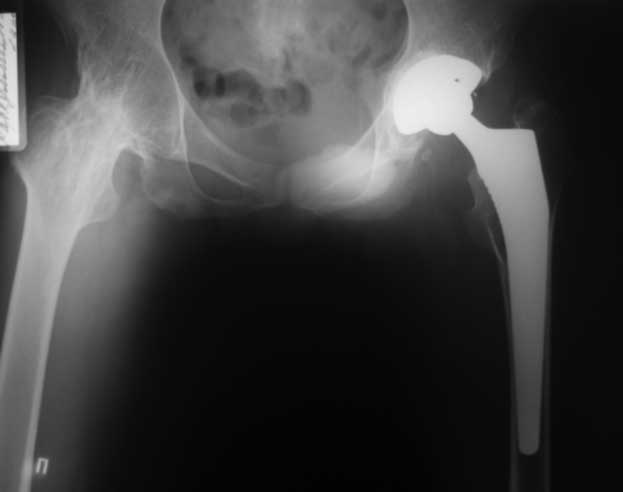

Уважаемые коллеги. пациент, страдает ревматоидным артритом с детства, ранее докладывался... костный анкилоз т/б суставов. 4 месяца назад THR левого т/б сустава, движения в т/б суставе приличные - с/р 90/5/0, движения в коленном суставе ухудшились - с/р 120/45/0. В настоящее время конечность неопорна из-за сгибательной кнтрактуры в к/с Вопросы о дальнейшей тактике лечения (пациенту 28 лет):1. рассматриваются варианты остеотомий (бедра, б/б кости), насколько это целесообразно, учитывая необходимость артротомии (остеофиты), каков может быть ожидаемый результат? варианты остеотомий (бедро или голень)?2. эндопротезирование к/с: мягкотканный дисбаланс- достаточно будет релиза капсулы и связок или мышцы тоже (учитывая разгибание в т/б после эндопротезирования и натяжение мышц на уровне колена после этого) Чего опасаться и к чему быть готовым?3. другие варианты? ссылки на литературу?собств наблюдения?С уважением Максим Агалаков